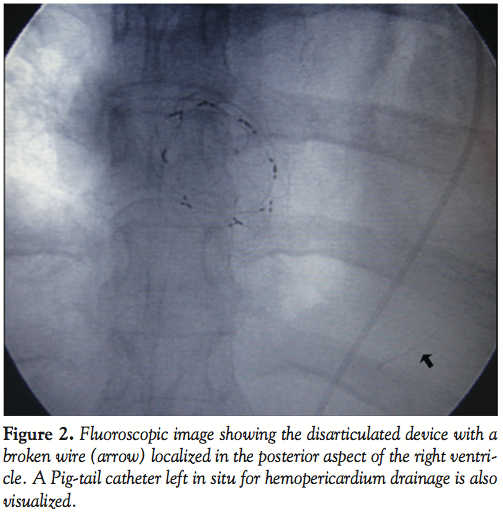

During her 6-month post-implantation visit, the patient complained of shortness of breath and easy fatigue since 20 days earlier. During physical examination, muffled heart sounds and hypotension were detected. A CXR showed large cardiomegaly and an electrocardiogram revealed right atrial enlargement and incomplete right bundle branch block. A Doppler echocardiogram showed a large circumferential pericardial effusion. A TEE was performed and a larger shunt measuring 8 mm in diameter at the anterosuperior rim was discovered with distortion of the device with

abnormal orientation of some wires (Figure 1). Fluoroscopy was performed in different angles and compared with the initial images obtained the day of implantation. This comparative study showed a disarticulated device with a portion of a wire fractured, separated from the device and migrated inferiorly. It was unclear if this wire was located either in the right ventricle (RV) or in the pericardial space (Figure 2).